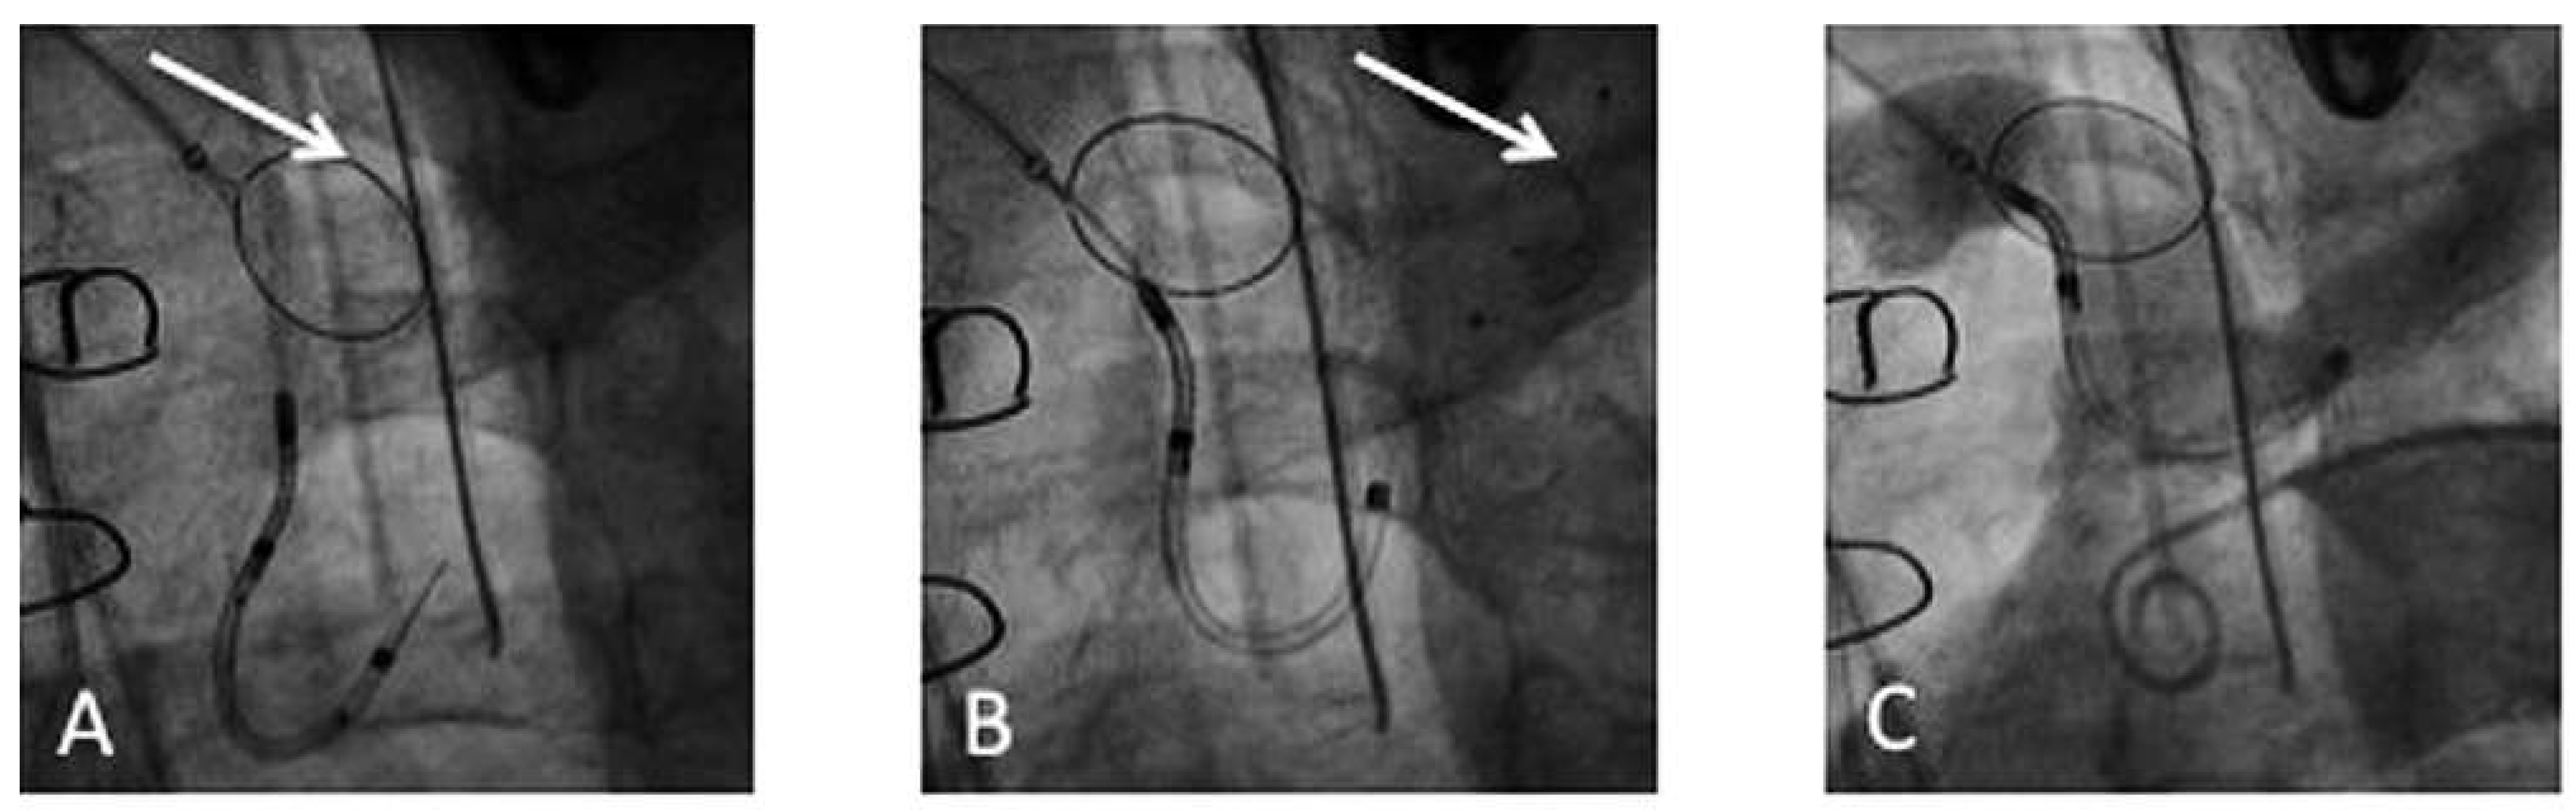

The Claret CE Pro™ device (Claret Medical Inc., Santa Rosa, CA, USA) is introduced via right radial or brachial access. It contains one filter basket to be deployed in the brachiocephalic trunk, and allows introduction of a standard filter wire to the left carotid artery [17]. The system consists of a 6 French sheath, a delivery system and the brachiocephalic filter (Figure 4). The first generation device was modified in order to allow introduction over a 0.014’’ guidewire and by modifying the bend of the distal steerable tip for antegrade probing of the left carotid artery. After deployment of the proximal filter in the brachiocephalic trunk, the distal tip of the delivery system is advanced to the aortic arch and positioned in a way to allow placement of the distal filter in the left carotid artery (Figure 5 and Figure 6).

The proximal filter is made of a porous polyurethane membrane and a nitinol frame. Anatomical requirements in the first-in-human study were a diameter of the brachiocephalic trunk of 9 mm and a left carotid artery diameter of at least 3 mm. While capturing of debris is appealing and the possibility to review what was captured by the device is illustrative and convincing, the device might be more demanding to deploy than the above described deflection devices: in the first-in-human study in 40 patients [17], delivery failure or imperfect deployment occurred in 25% of patients. The second generation device seemed to improve considerably on that (delivery failure reduced to 13%). Major complications occurred in 7.5% of patients, all related to radial or brachial access (1 dissection of the radial artery, 2 brachial pseudo-aneurysms; all treated surgically). After the TAVI procedure, macroscopic debris was present in >50% of patients, underlining the device’s effectiveness.

Figure 5. Deployment of the Claret CE Pro™: (A) Deployment of the first filter in the brachiocephalic trunk (arrow). (B) Deployment of the second filter in the left common carotid (arrow). (C) Confirmation of correct device position by contrast injection in the aortic arch.